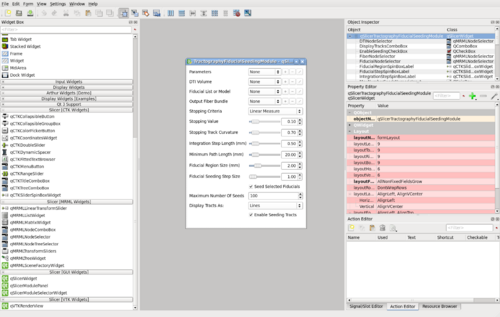

Dialogs

qSlicerWidgets

| qSlicerDiffusionTensorVolumeDisplayWidget |

|

Display widget for vtkMRMLDiffusionTensorVolume |

| qSlicerDiffusionWeightedVolumeDisplayWidget |

|

Display widget for vtkMRMLDiffusionWeightedVolume |

| qSlicerDTISliceDisplayWidget |

|

Widget to control vtkMRMLDiffusionTensorVolumeSliceDisplayNode |

| qSlicerMouseModeToolBar |

|

A toolbar to select mouse modes |

| qSlicerModuleSelectorToolBar |

|

A toolbar to select modules |